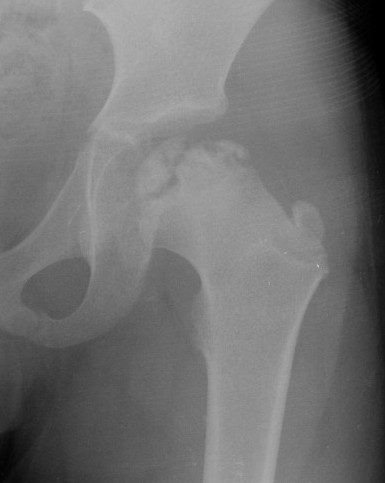

Femoral Varus Osteotomy (FVO)

Indications

Herring grade B or B/C

> 8 years at age on onset

Full containment of cartilaginous head

No hinge abduction